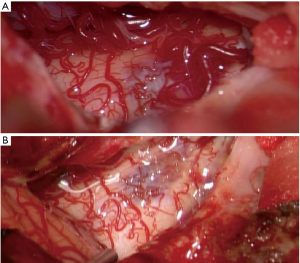

Subsequent cerebral MRI revealed a hematoma in the dorsolateral caudal medulla oblongata with intraventricular blood accumulation that was judged only few days old and sufficiently explained the lack of brainstem reflexes as well as the motor weakness (see Figure 4A). A perimedullary fistulous arteriovenous malformation (AVM) was identified as the cause of the bleeding (see Figure 4B). After partial endovascular coiling and subsequent surgical occlusion of the perimedullary AVM (see Figure 5) the patient was successfully extubated, but only gradually improved neurologically. He was finally transferred to a neurological rehabilitation center with severe right hemiparesis but completely recovered cardiac function. Follow-up examinations after 3 months showed no remains of the AVM and normal cardiac function.

Takotsubo cardiomyopathy is extremely rare in children and like in our case often initially mistaken for myocarditis or dilated cardiomyopathy (3). Previously described triggering conditions range from emotional stressors (9-11) to physical conditions (12-15). While the exact pathophysiologic mechanisms of Takotsubo cardiomyopathy remain unclear, the most distributed hypothesis implicates myocardial stunning. Sympathetic dysregulation and subsequent catecholamine excess supposedly cause direct toxic cardiomyocyte damage as well as coronary spasms in face of higher cardiac workload (5,16,17). Neurological and neurosurgical disorders as causes of Takotsubo cardiomyopathy seem less common in children than in adult patients (6) and include intracerebral hemorrhage, in some cases due to AVMs and fistulas (7,18-22). Like in our case, especially lesions affecting the medulla, home to important regulators of the autonomic function, can furthermore cause dysregulation of blood pressure and heart rate due to baroreflex failure resulting in cardiogenic shock (17,23,24).